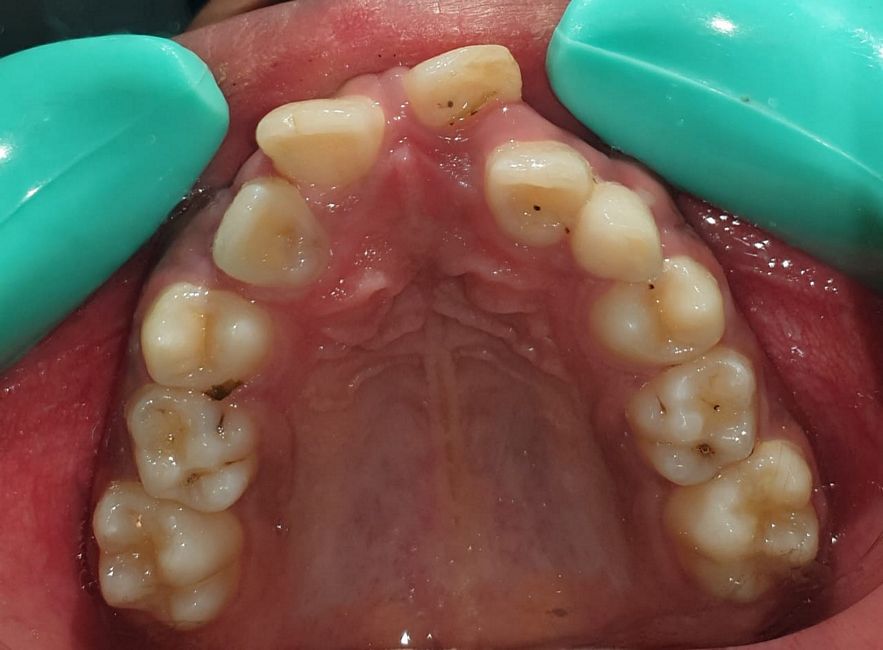

Case No: 23

Malocclusion Type: Class I Malocclusion.

Mechanics: MBT Mechanics.

Treatment: Class I Malocclusion with crowding in upper and lower anteriors treated by Non-extraction method.